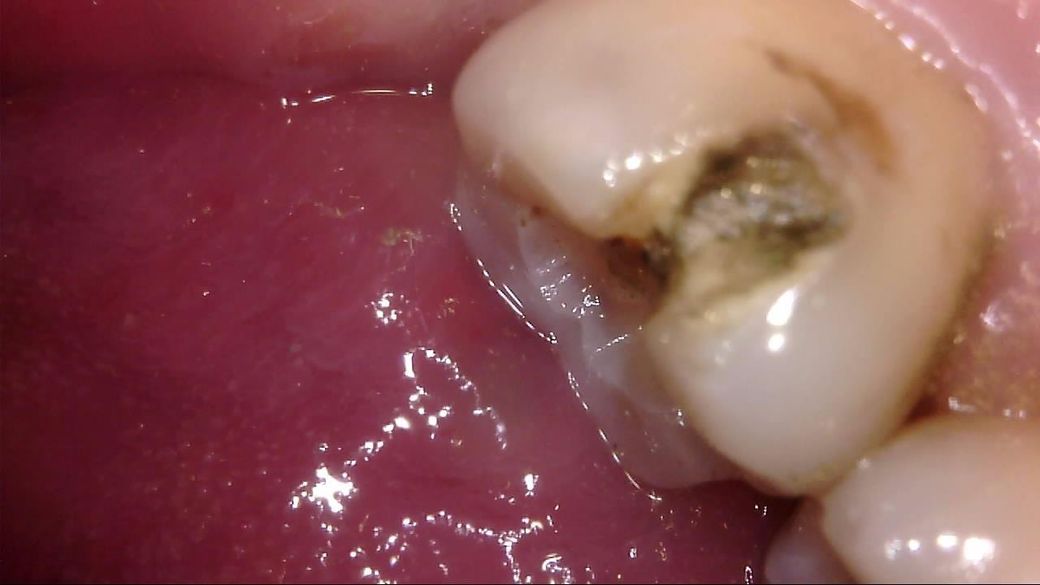

이차 우식이 상당히 깊게 발생하였는데, 치료 과정에서는 아래 사진과 같이 선생님께서 아래와 같이 일부 갈색 부분을 남긴 채 치아 삭제를 마치고 보철을 진행해 주셨습니다.

선생님께서는 "해당 부분은 착색 부위로, 이대로 덮어도 무방하다"라고 말씀 주셨고, 저 역시 더 이상 파고들어가면 신경치료가 예상되어 최선의 치료를 해 주셨다고 생각합니다.

다만 1) 해당 부위가 우식이 아닌 '착색'이 맞는지, 2) 해당 상태에서 보철물 안에서 추가 우식이 빠르게 진행될 가능성이 있는지, 3) 차라리 신경치료를 감수하고서라도 갈색 부분을 전부 없애는게 나았을지 불안감이 있는데, 관련하여 고견을 여쭙고 싶습니다.

사진에 보이는건 일단 착색과 2차 충치가 섞여 잇는거 같습니다. 충치를 제거하는 저스피드 기구로 제거를 해보기너 눌러 봐서 단단하면 충치가 아닙니다.

사진으로 보이는 부분은 충치에 어느정도 영향을 받은 부위는 맞습니다. 하지만 감염이 되어 있는것으로 보이지는 않습니다.

보철물로 치아를 씌우게 되면 해당부위에서 충치가 더 진행되거나 하지는 않습니다.

착색은 아니고 이환 상아질 남긴 것 같습니다 감염 상아질은 깔끔하게 다 제거 됐습니다

이정도면 진료 잘 받으신거 같습니다

충치가 맞는 것으로 보이지만, 직접 기구를 가져다 대보지 않으면 확신을 할 수는 없습니다.